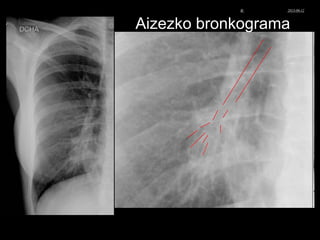

Aizezko bronkograma

© Xabier Zupiria, Andoni Bueno2013-06-12

Infiltradoa erdiko lobuloan (eskuina)

Erdi lobuloko neumonia